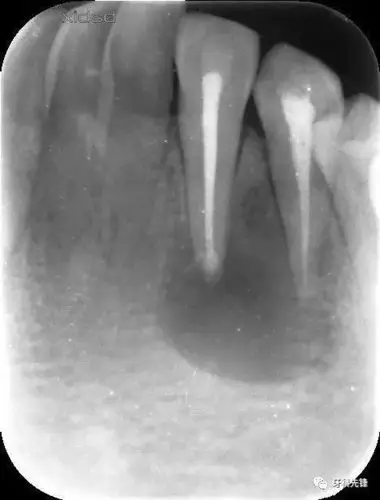

病例根管治疗囊肿刮除根尖切除mta根尖封闭同期完成